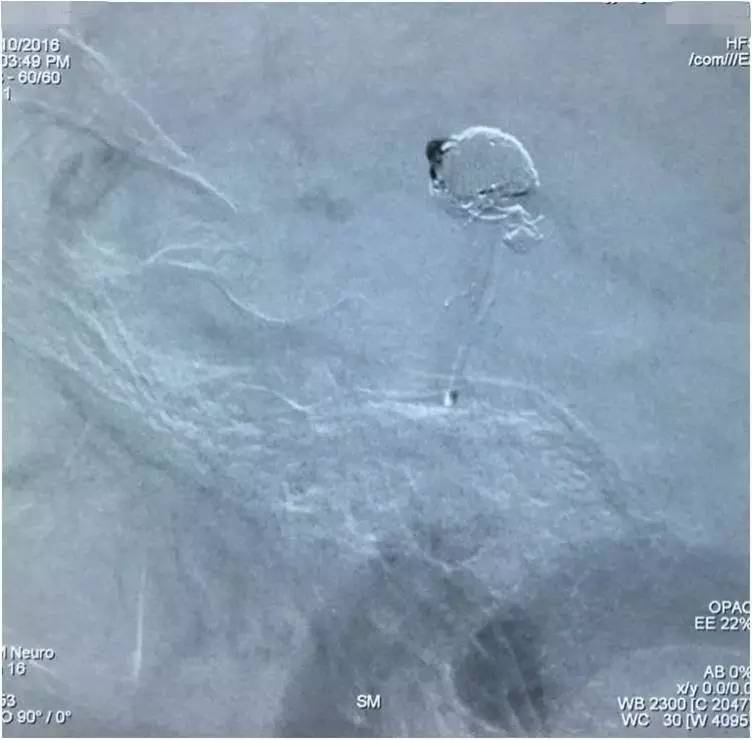

▼Headway17完成左小脑上动脉瘤的栓塞后,再经支架网眼导入右PCA,将第二枚LVIS JR 3.5*23支架跨瘤颈释放入右PCA-基底动脉,如此完成了Y型支架的释放,为基底动脉顶端动脉瘤的栓塞工程摆好了脚手架。

▼微导丝经支架内部弓背进入右PCA,Headway17微导管跟进,目的是加强第二枚支架(穿过了第一枚支架的网眼)的扩张性和贴壁性。

▼在Y型支架保护下经预置于瘤腔内的Echelon10微导管栓塞基底动脉顶端动脉瘤。

▼依次填圈,由于管头是朝向瘤腔右侧的,所以弹簧圈主要聚积在瘤腔右侧。

▼瘤腔左侧部还有空虚。

▼用微导丝将Echelon10的管头调整到瘤腔左侧空虚处继续“填空”。

▼瘤腔左侧部的空虚被填实,从整体看填塞的效果还是不错的。

▼然而,意外的是,造影评估显示动脉瘤顶端的子瘤还显影。